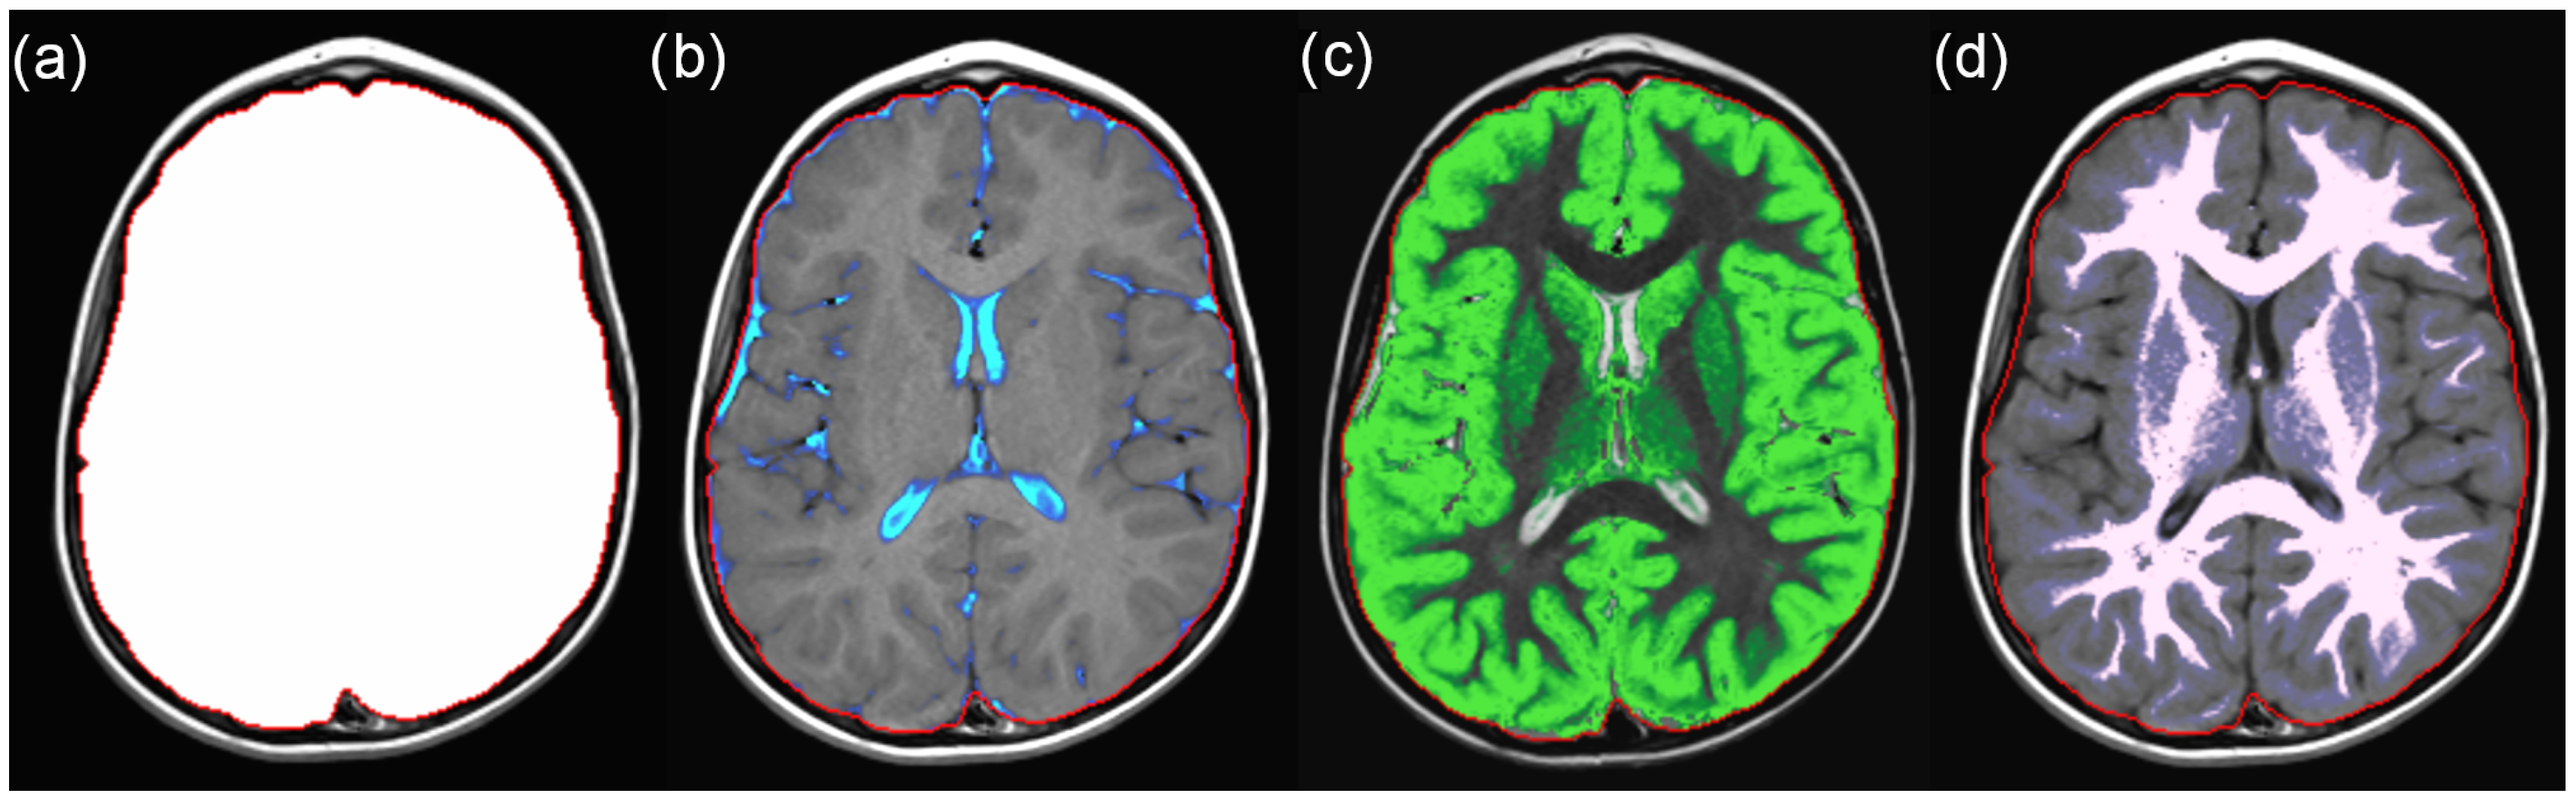

2.2. SyMRI Volume Measurements

2.3. Manual Volume Measurements